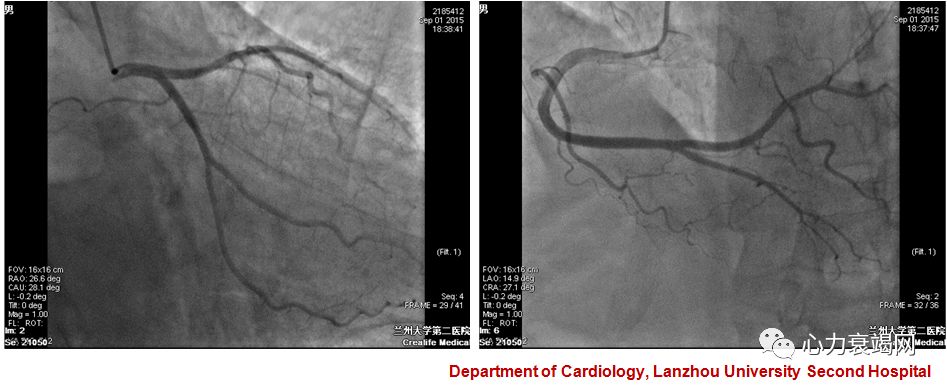

1.应激性心肌病 左室心尖部血栓

患者左心血栓形成原因?